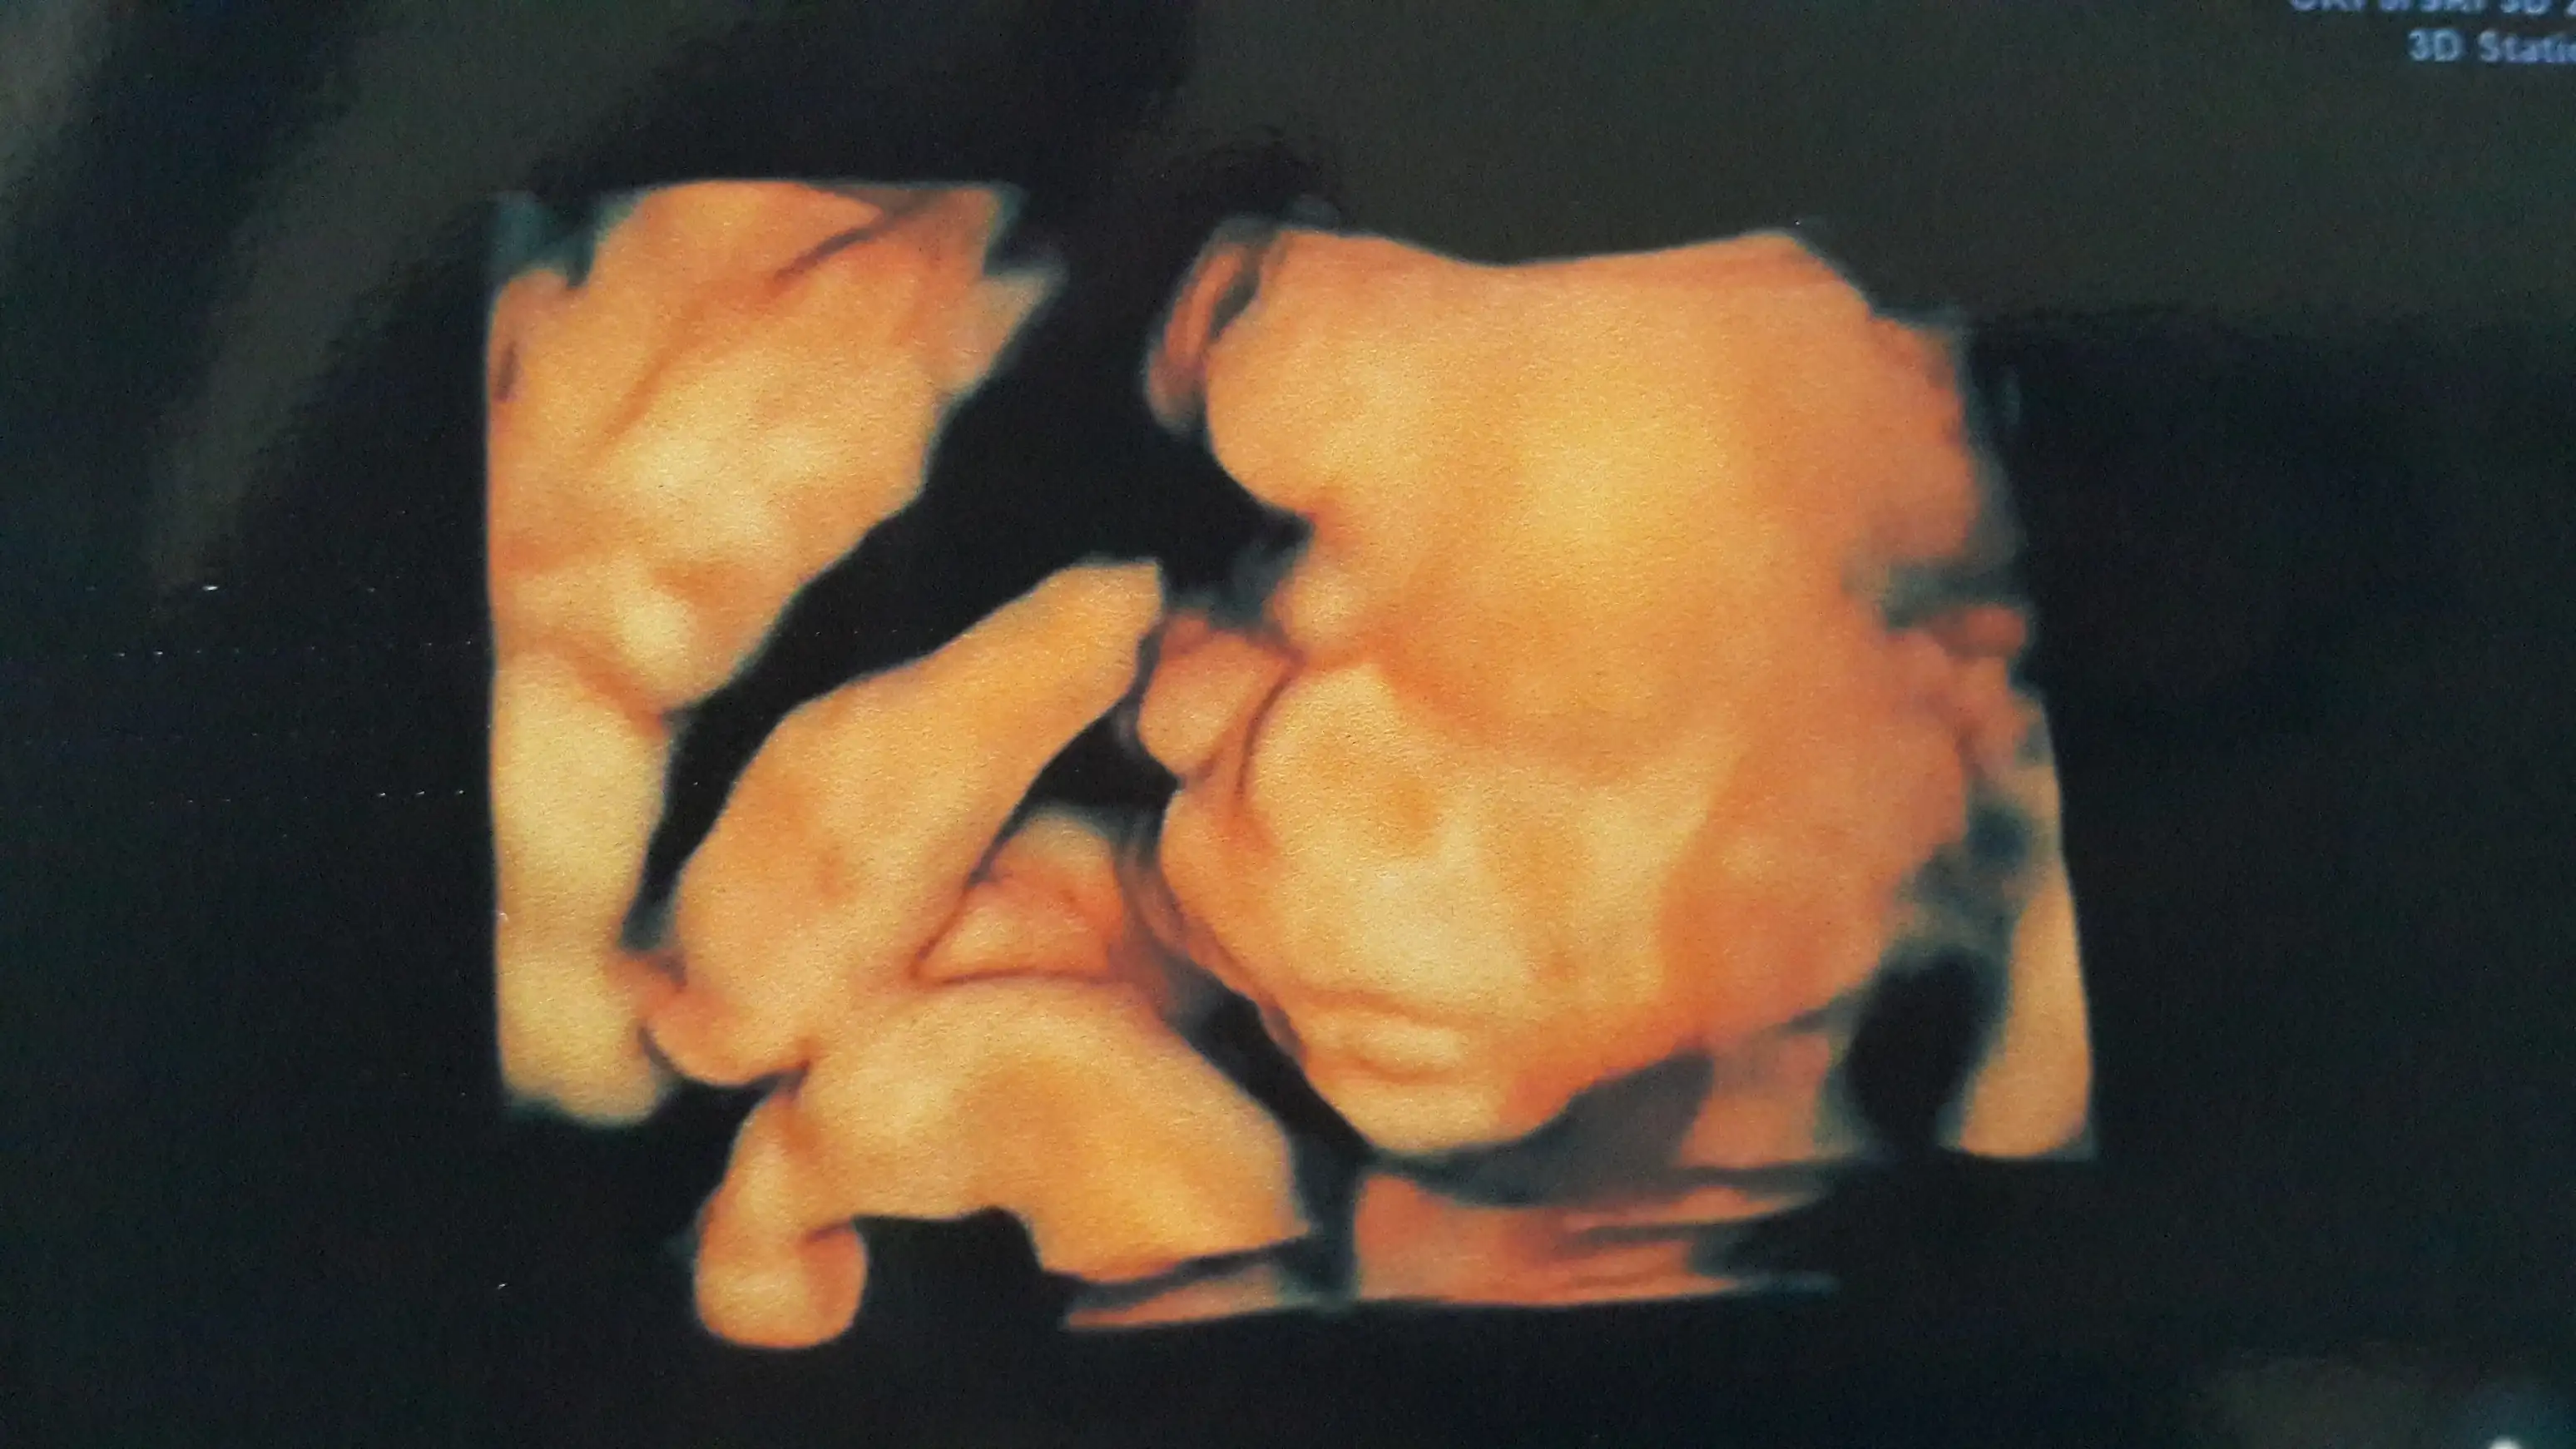

slm kızlar ayrıntılı usg mizi yaptırdık herşey normal allaha şükür oğluşum dr.u hiç yormadı her yerini rahatça gösterdi.daha ilk usg yi koyduğunda erkek bebiş dedi.artık değişmez heralde .yanliz göbek yağlı olunca 4 boyutlu resim almada zorlandı yinede yakaladı bir kaç poz.kilosuda 390 gr olmuş.

Ahhhh yavrum beniiiim:)gözlerim doldu ya ne güzel.Allahım hepsine sağlık ver yarabbim,sağlıkla zamanında gelsinler kollarımıza inşallah.gözün audın canım meleğin sağlıklıymış,açılışı sen yaptın:)slm kızlar ayrıntılı usg mizi yaptırdık herşey normal allaha şükür oğluşum dr.u hiç yormadı her yerini rahatça gösterdi.daha ilk usg yi koyduğunda erkek bebiş dedi.artık değişmez heralde .yanliz göbek yağlı olunca 4 boyutlu resim almada zorlandı yinede yakaladı bir kaç poz.kilosuda 390 gr olmuş.